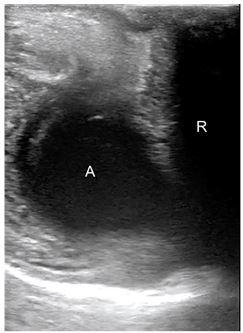

急诊科床旁经会阴超声诊断脓肿

Point-of-care Transperineal Ultrasound to Diagnose Abscess in the Emergency Department.

Perineal and rectal pain are common presentations in the emergency department (ED). In the majority of cases, clinical examination is sufficient to detect local anorectal pathologies. However, perianal and rectal abscesses and fistulas are often the primary concerns prompting diagnostic imaging in the ED. Currently, computed tomography is the preferred imaging modality. Recently, transperineal ultrasound has emerged as an optimal imaging modality for the diagnosis of perineal and perianal abscesses. We present a case in which point-of-care ultrasound accurately detected an intersphincteric abscess, and review the appropriate ultrasound technique to evaluate patients with suspected perianal and rectal abscesses.

摘要

会阴部和直肠疼痛是急诊科常见的症状。在大多数情况下,临床检查足以发现局部肛肠病变。然而,肛周和直肠脓肿及肛瘘往往是促使急诊科进行诊断性影像学检查的主要关注点。目前,计算机断层扫描是首选的影像学检查方式。最近,经会阴超声已成为诊断会阴部和肛周脓肿的最佳影像学检查方式。我们报告一例床旁超声准确检测到括约肌间脓肿的病例,并回顾评估疑似肛周和直肠脓肿患者的适当超声技术。